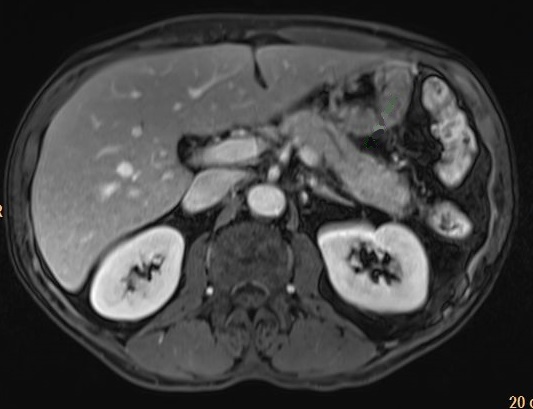

Sur les coupes IRM avec injection de

chelate de gadolinium le pancreas est rehaussement

homogene hyperintense . La rehaussement est visible

en meme temps avec les autre organe . Avec la recontructional

rapide en 3D on peut realise une veritable de

angiographie IRM au temps arteriel ou temp portal ce qui

peut remplace arteriographie des vaisseaux

pancreatiques |

De 40 -45s apres le debut de

injection de contrast intraveineuse la parenchyme du

pancreas se rehausse et apparait hyperdensite . Aspect

multi lobulaire de l'ishme et du queue du pancreas

est tres nette a ce temps . Image au dessus est TDM du pancreas

avec contrast intraveineuse en coupe axiale |